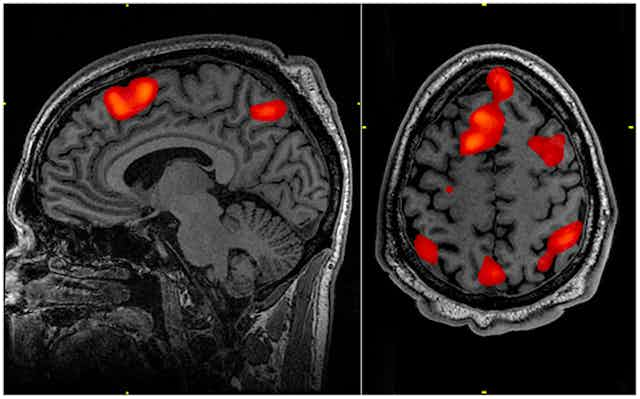

Such populist neuroscience is often based on a flawed model of what brain imaging can do. It tends to present it as a kind of “cinéma vérité”, offering real-time, instant access to clearly definable brain structures and functions. But brain maps are actually the end-product of a long chain of image-manipulation and complex statistical processing, specifically designed to highlight differences. They do not tell us what any one brain will do in any one situation.